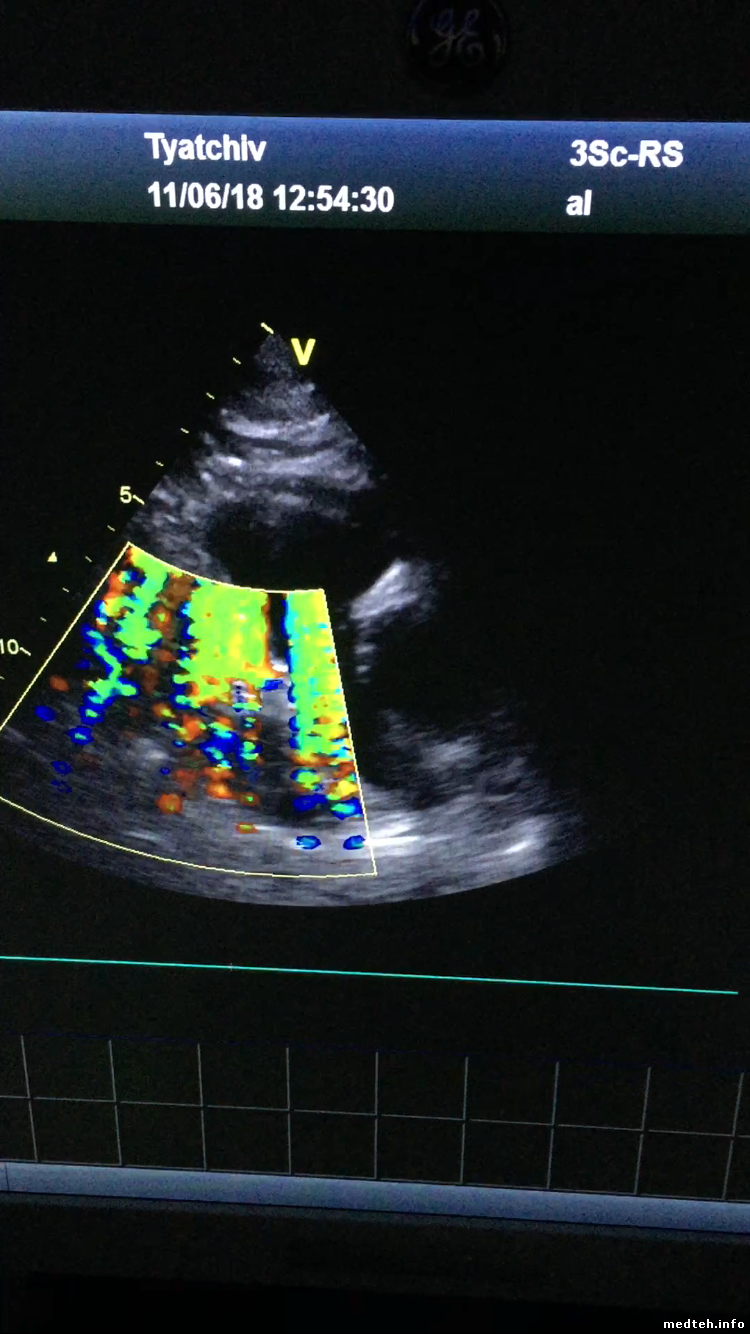

Кто может - посоветуйте, что делать. УЗИ аппарат "Vivid t8", покупал новым меньше года. В работе 6-7мес. Практически с самого начала на цветном допплере периодически появлялись помехи, то меньше, то больше.

Фото

0362389.jpg (169.9 Kb)

1964931.png (1.06 Mb)

Лично я, исходя из качества изображения на фото, следов падения не вижу.

ВАЖНО. В электронном секторе всегда работают одновременно все элементы. При нормально работающем датчике всегда есть помеховая полоса точно по центру. Там больше шумов и в В-изображении, и в доплеровских режимах. Причина чисто физическая. Для фокусировки луча по нормали к изображению требуется суммирование сигналов синфазно. Поскольку помеха всегда воздействует на элементы датчика синфазно, точно по середине изображения они суммируются наилучшим образом.

Это не является неисправностью датчика. Хотя разные экземпляры датчиков могут иметь различную помехозащищённость.

При увеличении усиления по В и колору, все шумы группируются в виде центральной полосы.

При касании поверхности датчика сухой рукой такие помехи обычно возрастают. Другой характерный признак нормальных помех - их постоянный уровень.

Обрыв кабеля или полное разрушение элемента никак не влияют на вид помех.

Если элемент полуразрушен и искрит, то помехи проявляются в виде "молний" на В, и широкими, иногда на весь экран, полосами повышенных помех в колоре, каждый раз в новых местах. Характер помех - импульсные и короткопериодические. Прикладывание руки существенно не влияет на уровень помех.